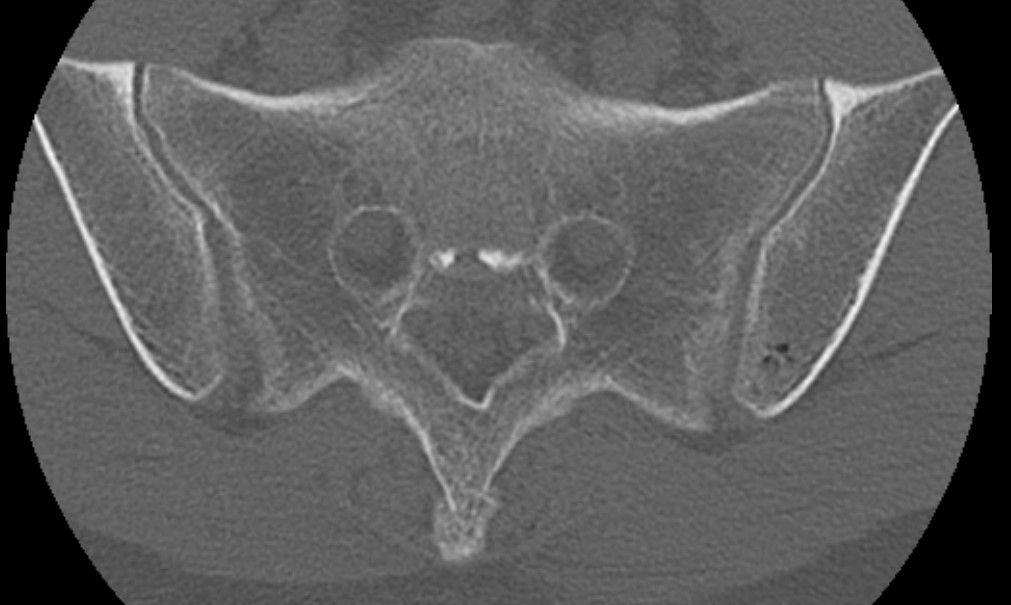

심할때는 1시간 걷다가 갑자기 골반과 옆구리가 알배기는듯이? 근육통이 심한듯이 느낌이와서 잠시 앉아서 쉬었습니다. ct영상으로도 디스크로 때문에 아프기엔 정상적인 정도라 하셔서 왜 아픈지 모르겠네요 . 현재 옆구리 좌,우 ,골반뒤쪽과 천추 꼬리뼈 또한 통증이 있으며 자고 일어나면 통증이 시작되고있습니다. 무엇때문인지 답답합니다. CT또한 촬영 했습니다.

x ray에 통증있는부분 표시 했습니다. 주로 뒤쪽으로 아픕니다. 3개월 됬습니다...직업상 앉아있는시간이 많습니다.

Pneumocyst, iliac side of left sacroiliac joint.